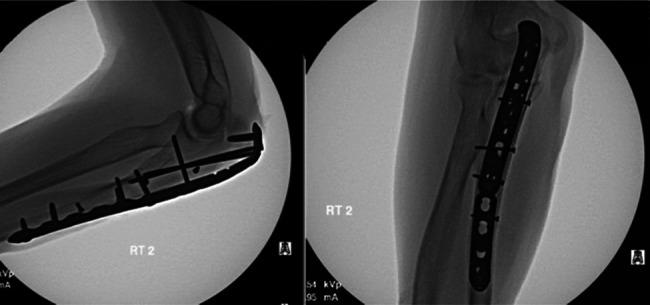

A total of five patients were included in this study. Causes for revision were acute implant failure (n = 2), aseptic nonunion (n = 1), and infected nonunion (n = 2). All patients eventually achieved bony union after revision. Two patients required an additional surgery because of Kirschner wire migration (n = 1) and symptomatic implant (n = 1). Average flexion was 126° (range 110 to 135) and average extension was 18° (range 5 to 30). All patients experienced restoration of extensor mechanism with full strength and returned to their previous working status. No other mechanical failures, surgical complications, or medical complications occurred.

Early results of revision open reduction and internal fixation for failed olecranon fracture fixation using tension band wiring demonstrated favorable outcomes and low complication rates. This technique may be used for revision of failed olecranon fixation.